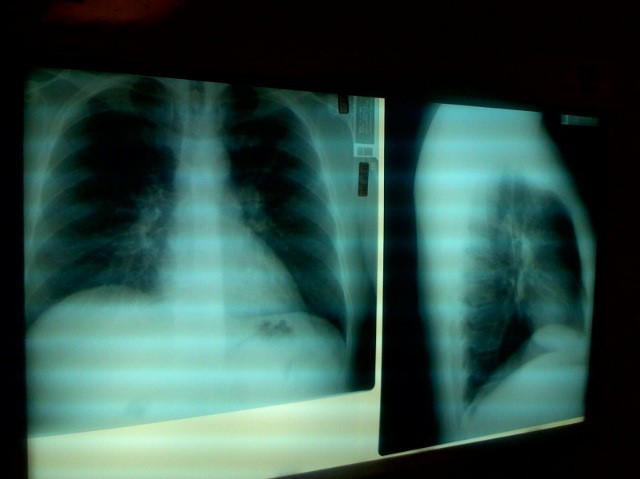

Чтобы поставить диагноз, врач назначит сбор анамнеза и аускультации, общий анализ крови, рентгенографию.